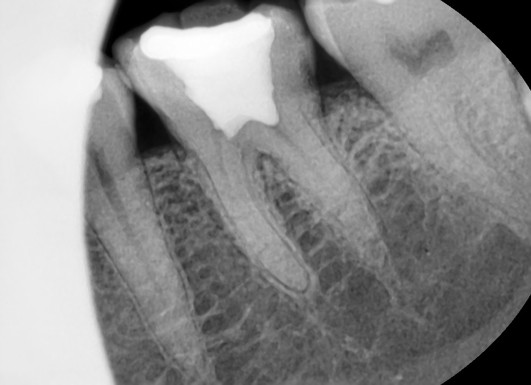

엑스레이 촬영 결과,

치아 머리 부분뿐 아니라

잇몸 아래 뿌리까지

금이 깊게 내려간 상태였습니다.

겉으로 보기에는

단순히 깨진 것처럼 보여도,

실제로는 치아 내부 전체가 갈라져 있어

수복(보존)이 불가능한 단계였습니다